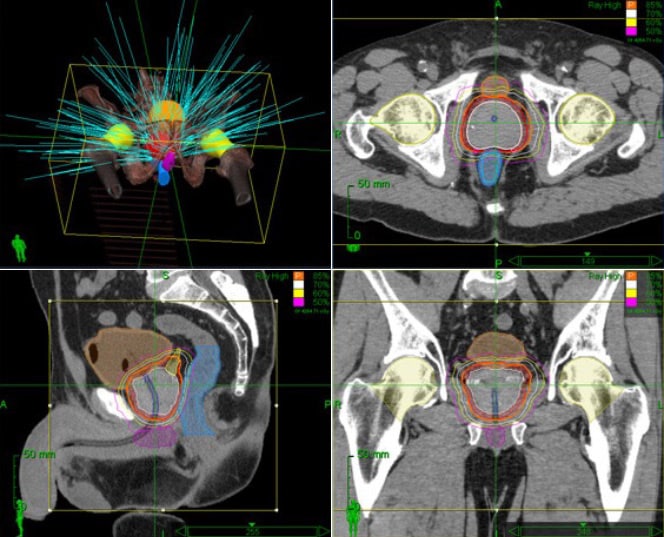

The Cyberknife differs from radiation therapy systems in that a conventional radiation source (high-energy photons) is attached to an industrial robot system, and thus freely movable in space. This allows a tumour in the patient’s body to be irradiated from all spatial directions with a sharply focused beam (“pencil beam”).

The CyberKnife’s robotic system thereby seamlessly delivers non-coplanar, non-isocentric and isocentric beams from a variety of angles. These unique delivery options generate conformal dose distributions and enable precise and effective treatments.

Of particular importance are the sharp dose gradients that are typical of the cyberknife. Because ideally, the tumour should be hit with maximum radiation dose, and the surrounding tissue with a dose of zero. Of course, this ideal dose distribution can never be achieved. But dropping as quickly as possible from the maximum dose in the tumour (e.g. 80 grays) to very low doses of 2-5 grays within a transition zone only 1 – 2 cm wide minimises the radiation dose to surrounding organs such as the bladder, rectum and nerves and vessels.